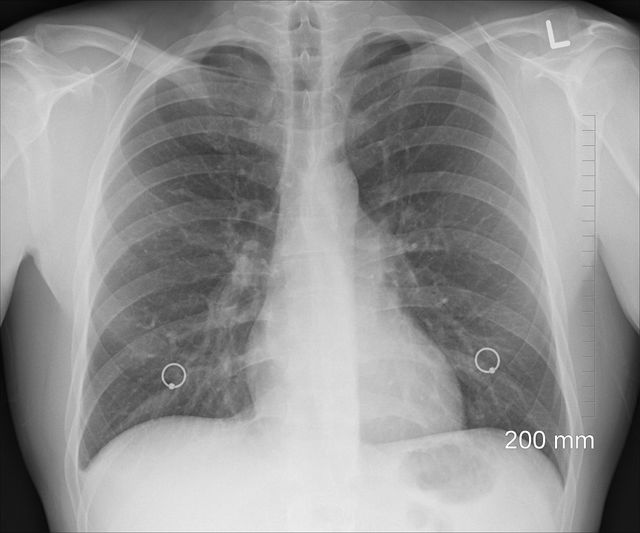

В лаборатории Челябинского областного клинического центра онкологии и ядерной медицины появился новый метод исследования, который может помочь пациентам с болезнью легких.

Как сообщает пресс-служба регионального минздрава, речь идет о тесте на наличие и определение уровня экспрессии белка PD-L1 в опухолях пациентов с немелкоклеточным раком легкого. Он открывает дополнительные возможности так называемого персонифицированного лечения пациентов и использования инновационных иммуноонкологических препаратов. Челябинский онкоцентр вошел в число пяти лабораторий в России, которые обладают такой возможностью.

«Иммунотерапия в корне меняет картину в лечении рака легкого. Выживаемость при 4 стадии рака легкого очень низкая, больше половины пациентов погибают в течение первого года, а пятилетняя выживаемость составляет один процент. Новая терапия позволяет существенно увеличить продолжительность и качество жизни», - говорит заведующий торакальным онкологическим отделением ЧОКЦО и ЯМ Андрей Лукин.